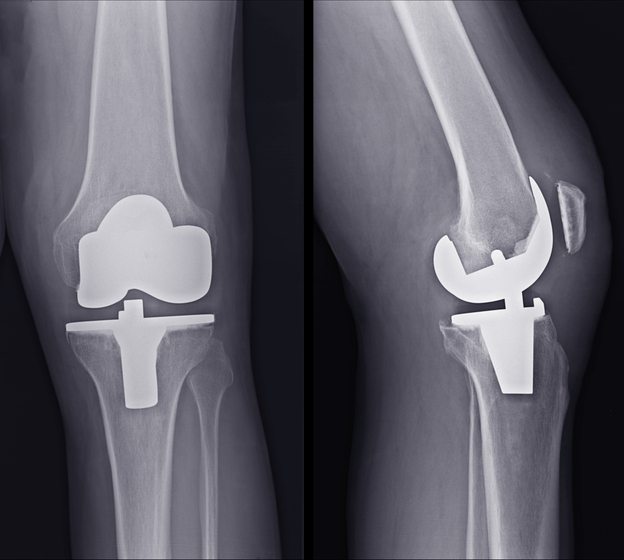

During knee replacement surgery, knee joints damaged by arthritis can be replaced with an artificial knee, also known as a prosthetic knee. A prosthetic knee can help restore mobility and reduce pain in the affected knee. When the joints of both knees are damaged, double knee replacement may be recommended.

When the cartilage has worn away in both knees, an artificial knee (called a prosthesis) can take its place. The surgery to implant both of the prosthesis is termed a Bilateral Total Knee Replacement. During this surgery, only the surface of the joint is removed, and the arthritic ends of the bones are shaved off and replaced with new metal and plastic surfaces. The knee replacement recreates almost normal function of the knee, and its main goal is to relieve pain. It may also help to restore motion of both knees and straighten the limbs.